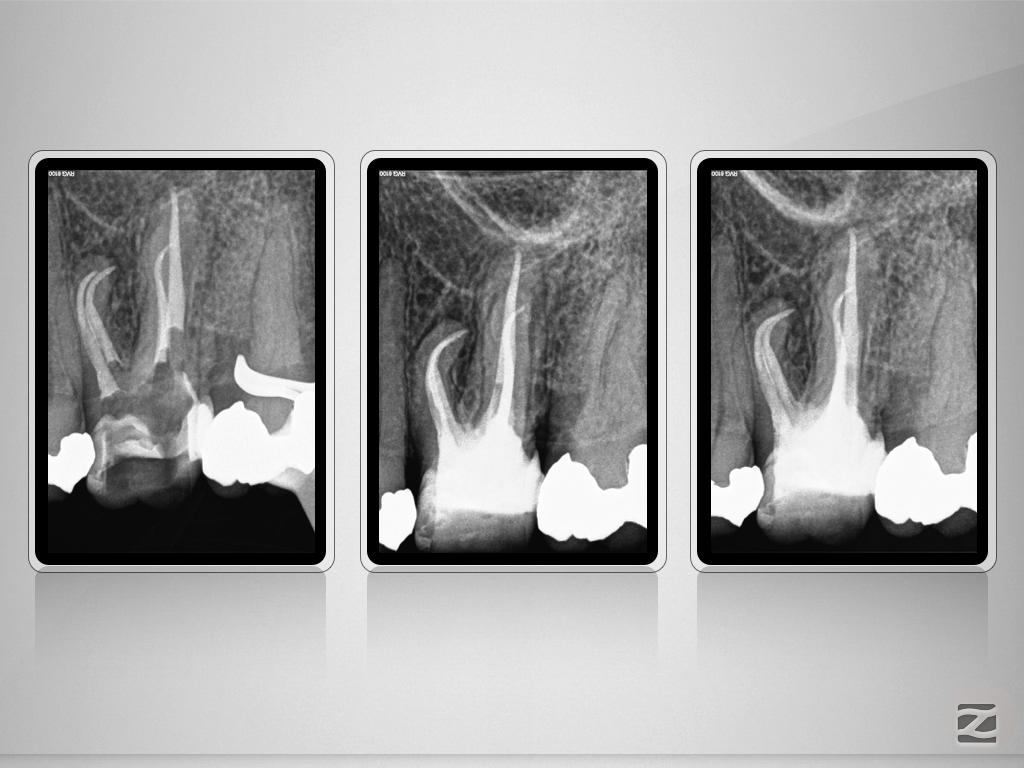

26D.006

Deutliche Krümmung und kein DVT!